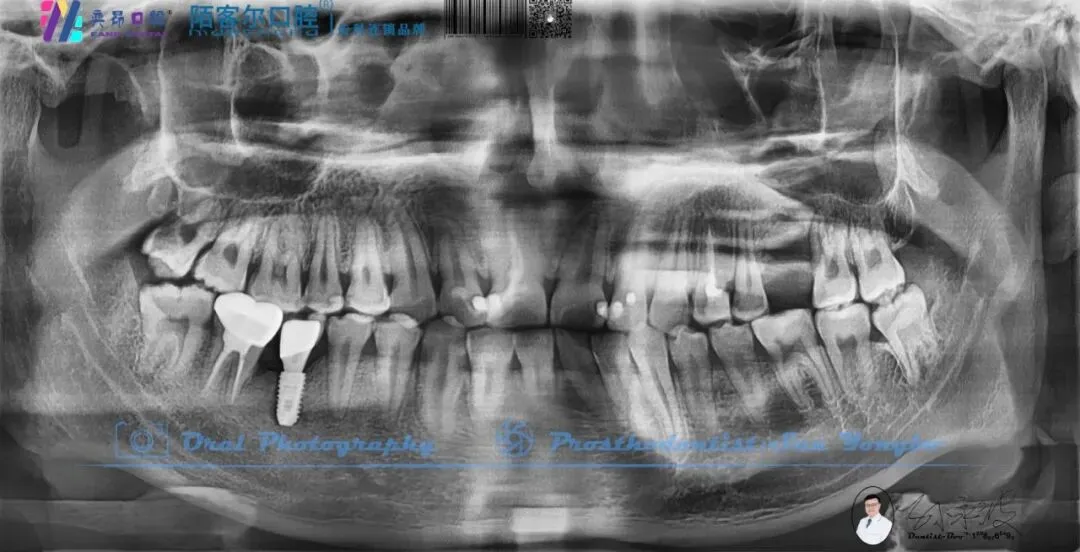

>【深圳牙医-孙永波】病例16丨右下后牙单颗缺失种植修复

【深圳牙医-孙永波】病例16丨右下后牙单颗缺失种植修复